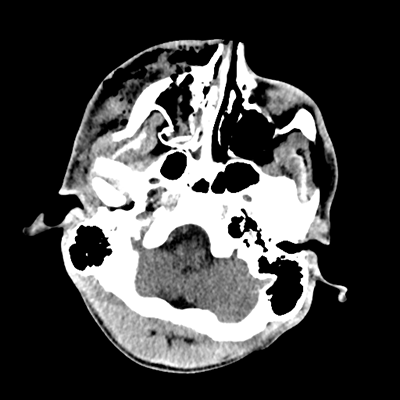

Initial vitals are notable for BP 111/67, HR 119, SpO2 100%, T 37.8C. She undergoes a whole-body CT scan. Trauma surgery also evaluates her. She has a zygomaticomaxillary complex fracture, comminuted fracture of her humerus, and fractures of ribs 2-6. Her non-contrast head CT is shown below. Plastic surgery evaluates her and recommends non-emergent operative repair of her facial fracture.

The patient has sustained multicompartmental hemorrhages—small amounts in the parenchymal, subarachnoid (mainly right frontal), subdural (right frontal, anterior temporal in particular), and intraventricular (layering in the right occipital horn) spaces. It’s a more subtle finding, but you can also see that the right hemispheric convexity has less sulcation, suggestive of cerebral edema on that side. There’s the right frontal contusion with hemorrhage there. There are also two small IPHs, in the right thalamus and left internal capsule. What do these represent? Likely diffuse axonal injury (DAI).